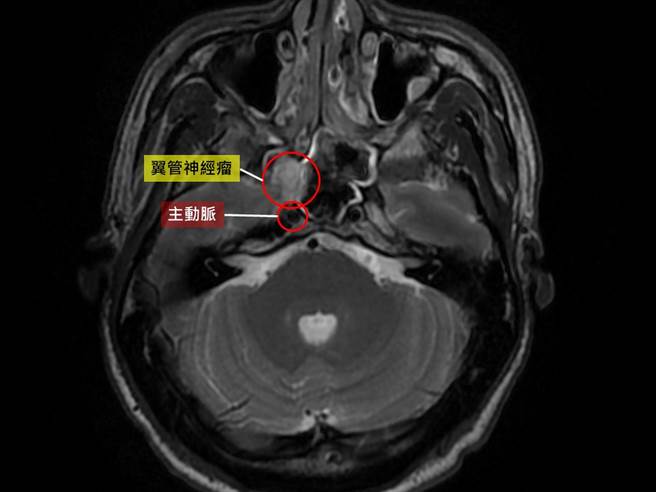

影像檢查發現張先生的翼管神經瘤緊鄰動脈,必須一點一點剝除腫瘤,避免大出血。(台中慈濟醫院提供/王文吉台中傳真)

張先生翼管神經瘤位於翼顎窩,靠近眼窩、顱底與主動脈,傳統開顱手術或放射線治療都有傷害顏面神經與血管疑慮。許原禎與病人討論後,採用內視鏡微創手術剝除腫瘤。

第二階段腫瘤手術,從前階段手術建立的通道,以內視鏡由後往前摘除腫瘤。許原禎表示,因腫瘤位在顱底、眼窩並貼近主動脈,加上腫瘤已沾黏翼管神經,剝除不易,手術深度更須戰戰兢兢,一點一點從翼管神經上剝除腫瘤,避免傷害主動脈造成大出血。